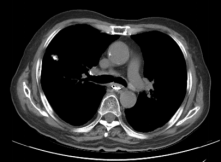

Before Photon Radiotherapy Before Carbon Ion Radiotherapy After Carbon Ion Radiotherapy 1 Month After CarboRadiotherapy

Before Photon Radiotherapy Before Carbon Ion Radiotherapy After Carbon Ion Radiotherapy